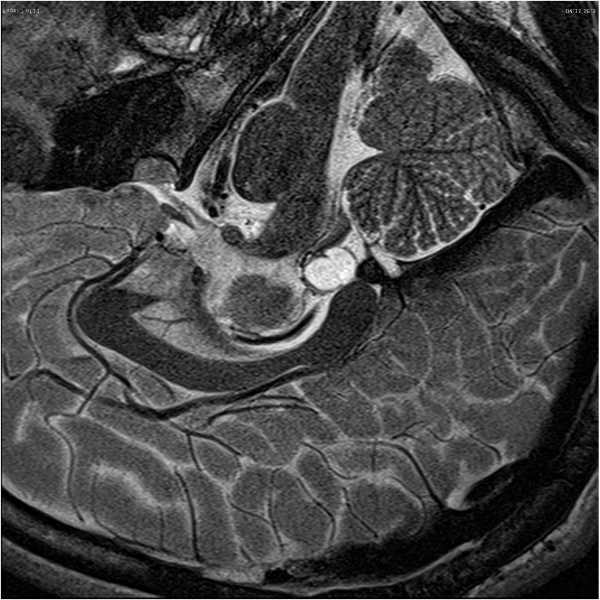

• 松果体区胶质母细胞瘤案例解读一则

松果体区胶质母细胞瘤案例解读一则

2021-01-25 17:33:23

多形性胶质母细胞瘤(GBM)很少在松果体区发现。本文介绍了一个松果体区原发性胶质母细胞瘤(GBM)的病例,讨论了临床过程、影像学表现和治疗方法。根...